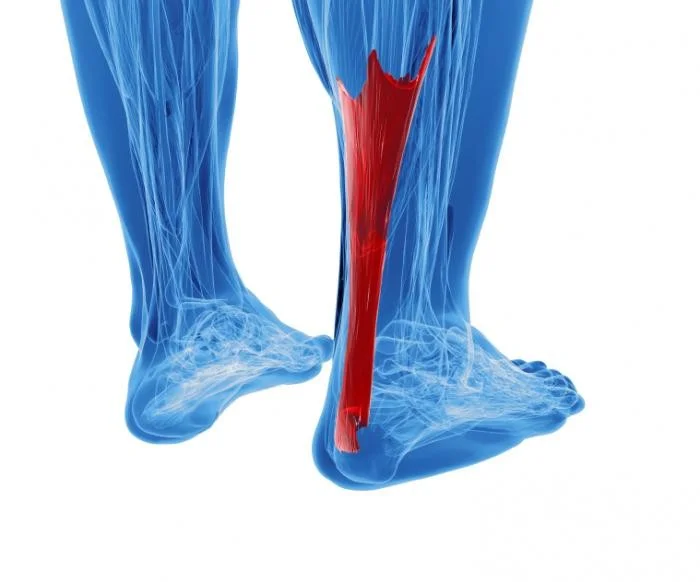

Achilles Tendinitis

Overview

Achilles tendinitis is a condition characterized by inflammation of the Achilles tendon.

Types of Achilles Tendinitis

- Insertional

- at insertion into Calcaneum

- not related to activity

- Non-insertional

- within the tendon

- in younger active patients

Complications of Untreated Achilles Tendonitis

- Achilles tendon pain should be treated

- If left untreated, the tendon can become weak, frayed, and eventually may rupture